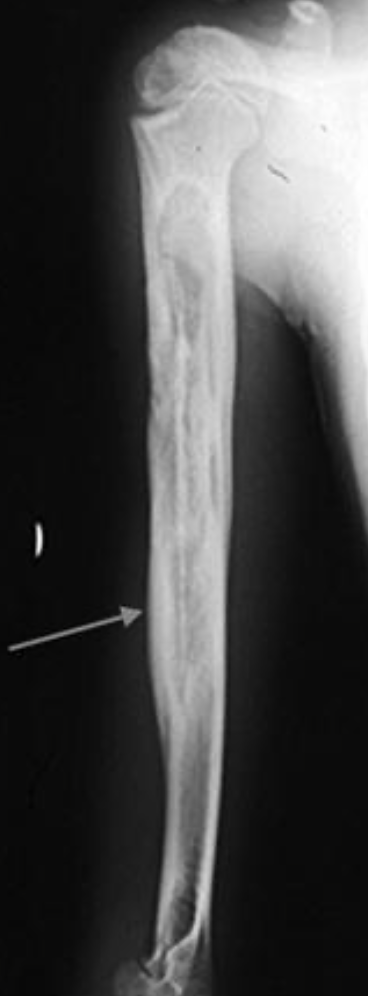

A patient presents with ?osteomyelitis. An MRI is performed.

What does the arrow point at? [1]

A

involucrum: formation of new bone around an area of bony necrosis

sequestrum: devitalized bone that serves as a nidus for infection